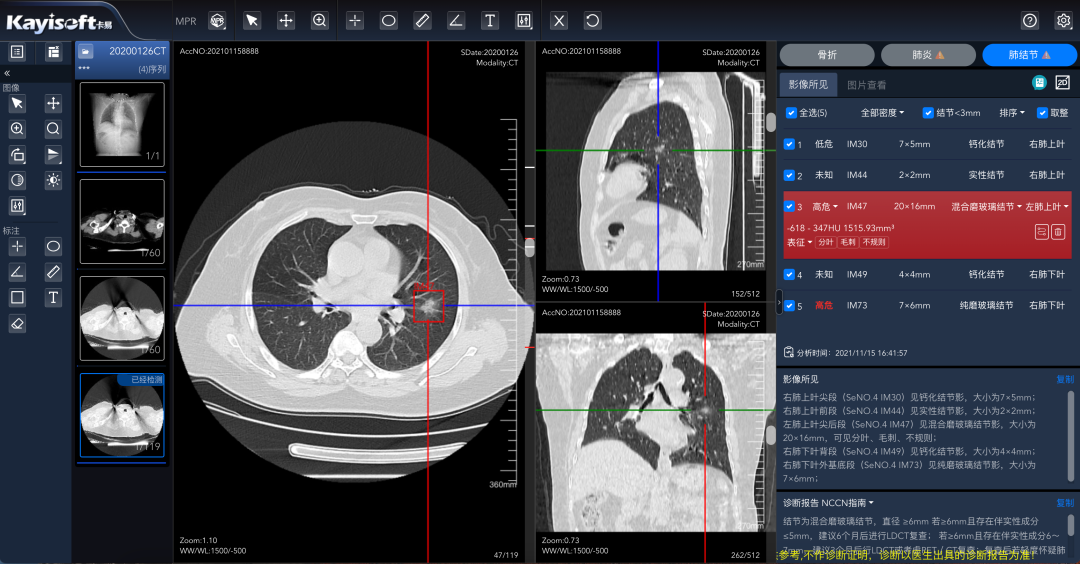

¡®¿µ½¡ÔƼ졯ƽ̨µÄÁÁµãÔÚÓÚÆäǿʢµÄAIÖÇÄÜÕï¶Ï¹¦Ð§¡£¡£¡£¡£¡£¡£¡£¸Ãƽ̨Äܹ»×Ô¶¯Ê¶±ðÓ°Ïñ£¬£¬£¬£¬£¬Ìṩ²¡ÔîÖÇÄÜÕï¶ÏÆÊÎö£¬£¬£¬£¬£¬²¢ÌìÉúͼÎĽṹ»¯±¨¸æ¡£¡£¡£¡£¡£¡£¡£Ïà½ÏÓڹŰåµÄÈ˹¤Á÷³Ì£¬£¬£¬£¬£¬Õâһϵͳ²»µ«ÄܽÚÔ¼´ó×Úʱ¼ä£¬£¬£¬£¬£¬Ìá¸ßЧÂÊ£¬£¬£¬£¬£¬»¹ÄÜÔÚÒ»¶¨Ë®Æ½ÉϱÜÃ⩼ìºÍÎóÕïµÄ±¬·¢¡£¡£¡£¡£¡£¡£¡£ÓÉ´Ë£¬£¬£¬£¬£¬Ò½ÁÆ×ÊÔ´Äܹ»ÊµÏÖ¼¯Öй²ÏíºÍ¸ßЧÉèÖ㬣¬£¬£¬£¬Èû¼ÕßµÃÒÔÏíÊܼÒÃſڵġ°AI+¡±¿µ½¡ÊØ»¤¡£¡£¡£¡£¡£¡£¡£

»ùÓÚÇøÓòÓ°ÏñÔÆµÄCT·Î½á½ÚAIÆÊÎö

ÕâÒ»Ó¦ÓÃͨ¹ýÓ°ÏñÊý¾ÝÔÆ»¯ÖÎÀíÊý¾ÝͳһÊÕÂÞ£¬£¬£¬£¬£¬ÊµÏÖÒÔÊý¾ÝΪ»ù´¡£¬£¬£¬£¬£¬ÍŽá AI ÆÊÎöЧÀÍ£¬£¬£¬£¬£¬ÊµÏַνá½ÚÖÇÄܱê×¢£¬£¬£¬£¬£¬½µµÍ©Õï¡¢ÎóÕïµÄ¸ÅÂÊ£¬£¬£¬£¬£¬½«ÕïÆ¬Ê±¼ä´Ó¹Å°åµÄ5·ÖÖÓ£¬£¬£¬£¬£¬Ëõ¶Ìµ½ÁË2-3·ÖÖÓ¡£¡£¡£¡£¡£¡£¡£

ͨ¹ýÊм¶Í³½¨¡¢¸÷µØÊ¹Óõķ½·¨£¬£¬£¬£¬£¬Ï²ãÒ½ÁÆ»ú¹¹Í¬Ñù¿ÉÒÔʹÓøÃÈ˹¤ÖÇÄÜÊÖÒÕ£¬£¬£¬£¬£¬¼«´óµÄÌáÉýÁËϲãɸ²éЧÂÊ£¬£¬£¬£¬£¬ïÔ̼²²¡¼ì²éÎóÕ©ÕïÂÊ£¬£¬£¬£¬£¬µÖ´ïÇøÓòÒ½ÁÆ»ú¹¹Ò½¼¼Ë®Æ½ÌáÉý£¬£¬£¬£¬£¬Ìá¸ßÇøÓòסÃñ¿µ½¡ÉúÑÄˮƽ¡£¡£¡£¡£¡£¡£¡£